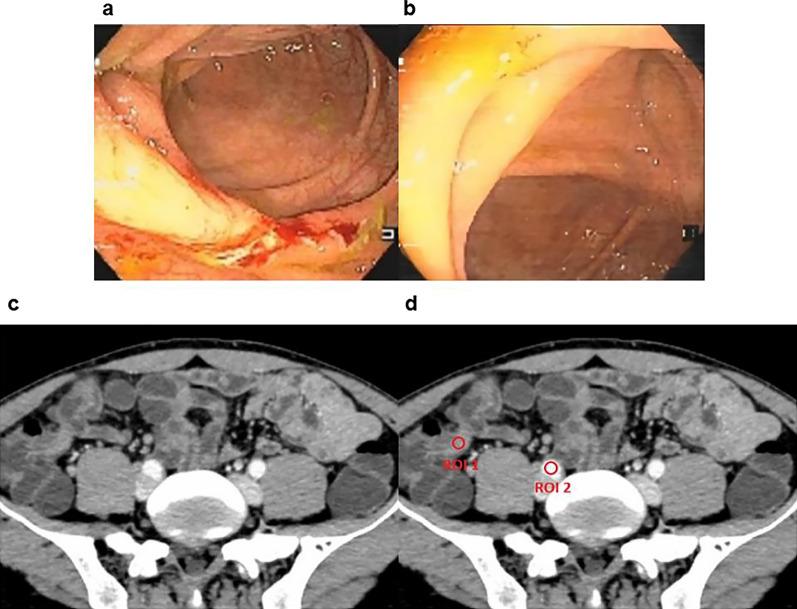

In this retrospective study, 94 patients with diagnosed CD underwent endoscopy and dual-energy CT enterography (DECTE) at the post-infliximab treatment review. Two radiologists reviewed DECTE images by consensus for assessing diseased bowel segments of the colon or terminal ileum, and the NIC was measured. Patients were divided into transmural healing (TH), MH and non-MH groups. The diagnostic performance of the MH and non-MH groups with clinical factors and NIC was assessed utilizing receiver operating characteristic (ROC) curve analysis.

Of the 94 patients included in our study, 8 patients achieved TH, 34 patients achieved MH, and 52 patients did not achieve MH at the post-IFX treatment review. The area under the ROC curve (AUC), sensitivity, specificity, and accuracy values were 0.929 (95% confidence interval [CI] 0.883-0.967), 0.853, 0.827, and 0.837, respectively, for differentiating MHs from non-MHs, and the optimal NIC threshold was 0.448. The AUC of the combined model for distinguishing MHs from non-MHs in CD patients, which was based on the NIC and calprotectin, was 0.964 (95% CI 0.935-0.987).